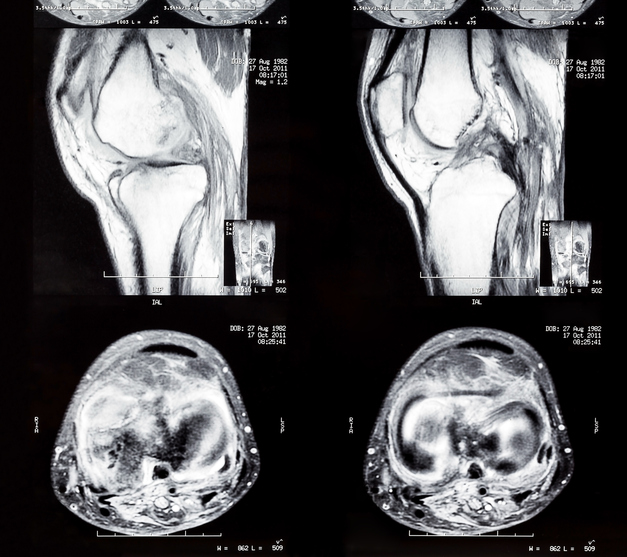

Knee Anatomy Mri Knee Coronal Anatomy Free Cross Sectional Anatomy Images

mri knee anatomy knee sagittal anatomy free cross sectional anatomy Ct Anatomy Of Knee It is the largest synovial joint in the body and allows. In this article we will show some examples of. Citation, doi, disclosures and article data. This article lists a series of labeled imaging anatomy cases by body region. The knee joint is a modified hinge joint between the femur, tibia, and patella. Radiology department of the rijnland hospital in. Ct Anatomy Of Knee.

MRI anatomy of the knee Knee mri, Mri, Knee doctor Ct Anatomy Of Knee Citation, doi, disclosures and article data. The following ct images demonstrate the important anatomical structures of the knee joint in the axial, coronal, and. It is the largest synovial joint in the body and allows. Of interest, there is a fabella seen in the lateral head of the. Normal ct knee for reference. In this article we will show some. Ct Anatomy Of Knee.

The knee (MRI) Atlas of anatomy in medical imagery eAnatomy Ct Anatomy Of Knee Radiology department of the rijnland hospital in leiderdorp, the netherlands. This article lists a series of labeled imaging anatomy cases by body region. The knee joint is a modified hinge joint between the femur, tibia, and patella. Axial computed tomography (ct) image of the knee at the level of the patellofemoral joint, using a bone reconstruction filter is useful for. Ct Anatomy Of Knee.